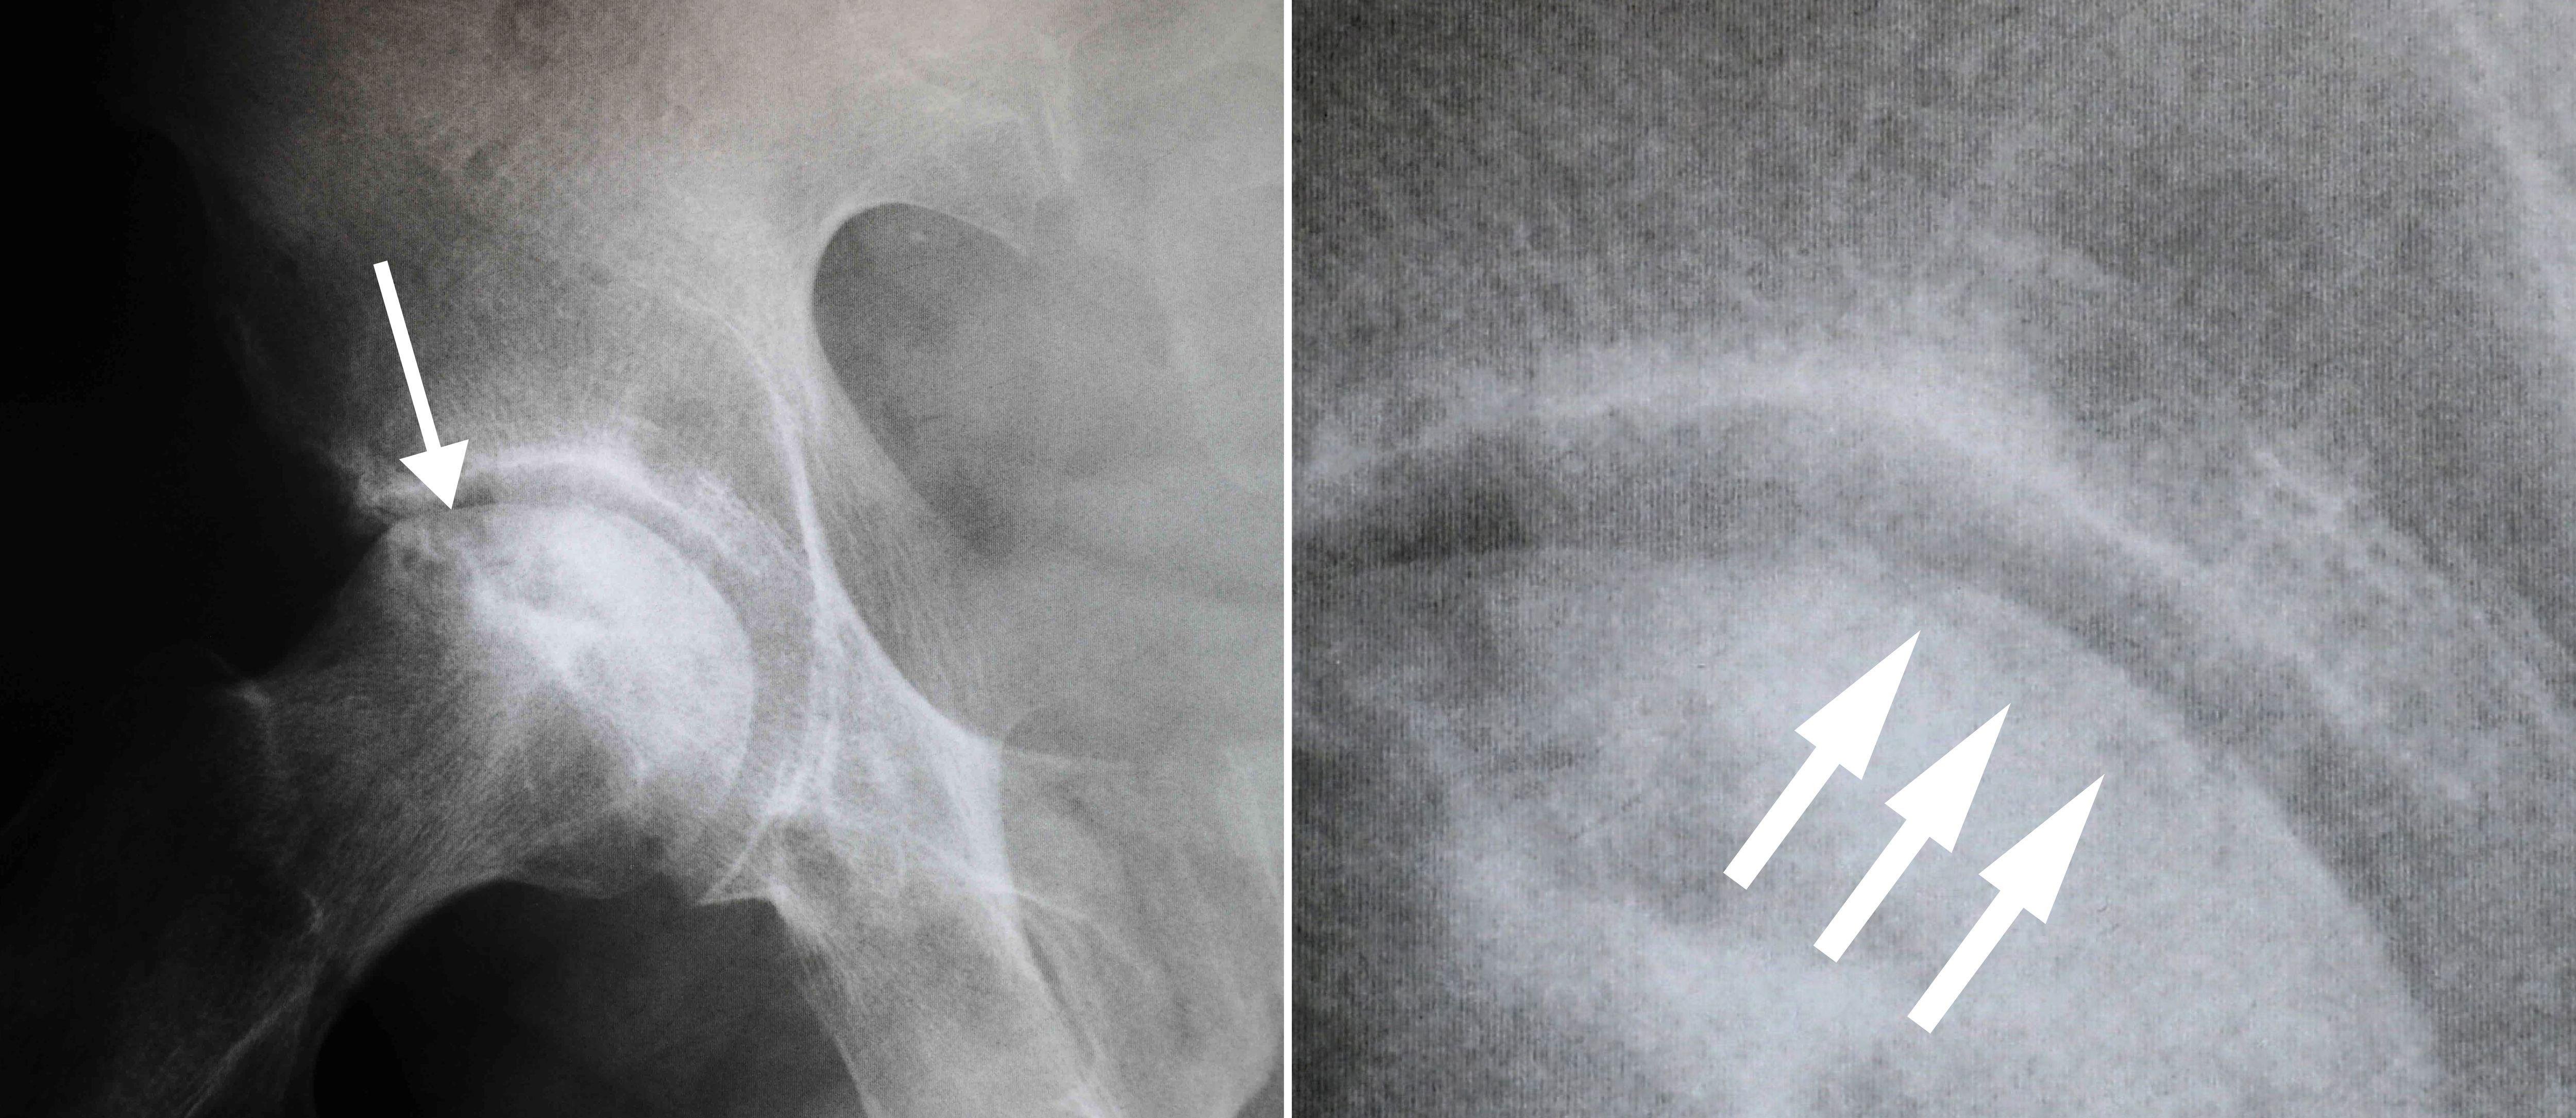

骨坏死通常被视为楔形区域,在股骨头的上外侧部分具有致密的白色硬化边界。在侧视图中,通常可以在股骨头表面下方看到一条称为“新月征”的透明线。

(左)这张 X 光片显示髋部骨坏死。(右)当近距离观察时,X 射线显示出通常在股骨头塌陷之前看到的“新月征”